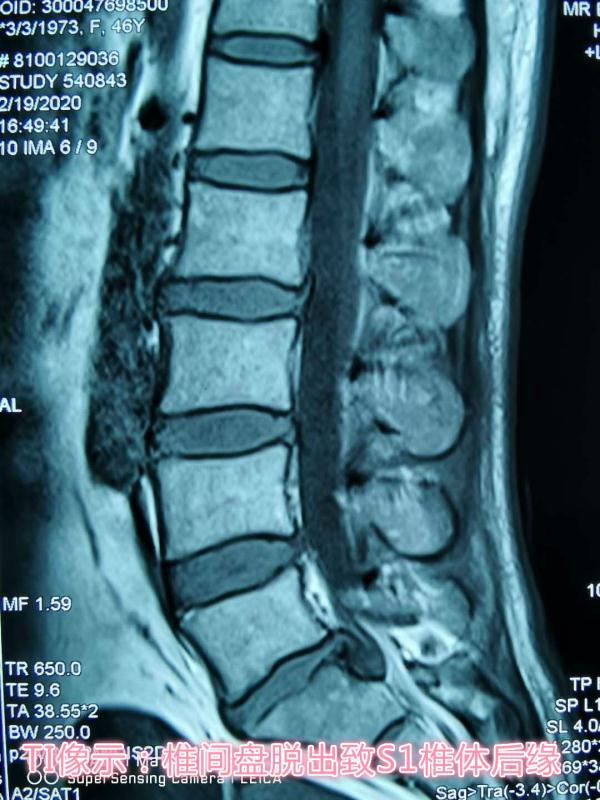

患者,女性,47岁,左下肢疼痛伴麻木1年,加重两月。入院后,骨科医护团队立即完善相关检查,仔细察看患者病情发展情况,为其制定了精准的治疗方案,同时向患者及家属详细讲解了手术的优势及术后的注意事项,患者及家属表示理解并同意手术。术中一切顺利,术后患者次日即可下地活动,大大缩短了传统Tlif术后需卧床三月的修复时间。